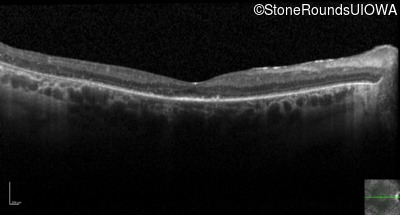

Optical Coherence Tomography - Right - 20/80 +1

Exemplar / OCT Stack